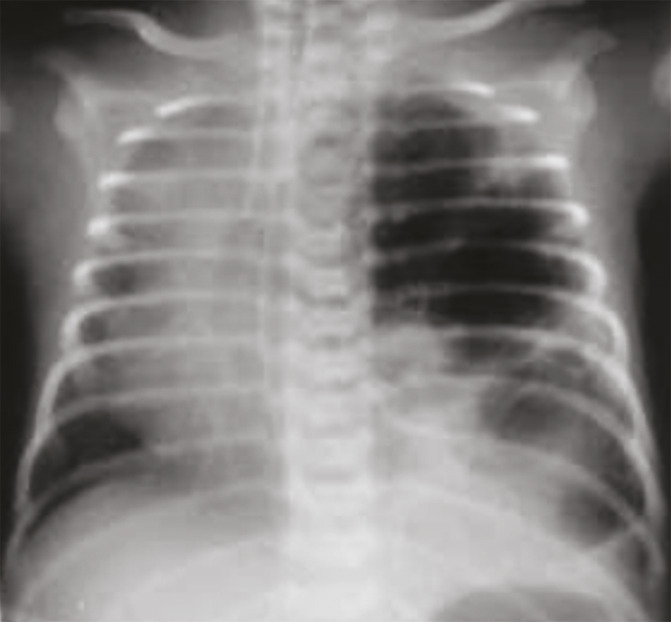

Le scanner thoracique ou tomodensitométrie (TDM) montre de multiples lésions kystiques au sein d’une condensation parenchymateuse pulmonaire prenant la quasi-totalité du poumon gauche, typiques d’une malformation adénomatoïde kystique classée type I de la classification d’Adzick (fig. 2).